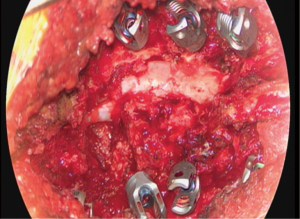

The patient underwent the anterior stage of her procedure without complication. The posterior annulus nor the posterior longitudinal ligament (PLL) were removed. The patient was extubated without complication and transferred to the postoperative care unit, where she was reporting some continuation of her right posterior leg pain, as well as some left anterior thigh numbness. The following day, she underwent her planned second stage T10-pelvis posterior spinal decompression fusion with O-arm navigated instrumentation. Standard open posterior approach was utilized. All screws were stimulated to indicate appropriate positioning and there was no evidence by any means for pedicle wall violation. Following this, open decompression was performed, including: partial decompressive laminectomy at L2, L3, L4, and L5 with total decompressive facetectomy at left L2/3, left L3/4, right L4/5. Bone morphogenetic protein (BMP), local autograft, as well as crushed cancellous allograft and submicron topography biphasic calcium phosphate granules were utilized to promote fusion. Rods were placed and final tightening was performed with appropriate positioning of implants. Final Valsalva to 40 mmHg was negative for any evidence of CSF leak and there were no complications noted intraoperatively (Figure 2). Two deep subfascial drains were placed in the area of the decompression and held to suction, with appropriate serosanguinous drainage.